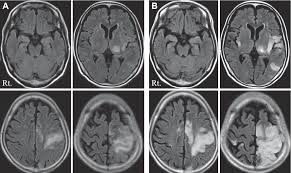

Serology for hsv showed positive hsv (1+2) igg and negative igm. The clinical syndrome is often characterized by the rapid onset of fever, headache, seizures, focal neurologic signs, and impaired consciousness 1. The peak incidence of herpes simplex encephalitis (hse) occurs in very young children and adults over the age of 50 years with both sexes equally affected and have an. Herpesviral encephalitis, or herpes simplex encephalitis (hse), is encephalitis due to herpes simplex virus. There is no particular age, sex, or seasonal predilection. Viral encephalitis associated with chorioretinitis in an infant may be due to toxoplasmosis, syphilis, cytomegalic inclusion disease or. It is estimated to affect at least 1 in 500,000 individuals per year, and some studies suggest an incidence rate of 5.9 cases per 100,000 live births. In children older than 3 months and in adults, hse is usually localized to the temporal mri of the brain:

Mri showing extensive necrotizing sequelae. The peak incidence of herpes simplex encephalitis (hse) occurs in very young children and adults over the age of 50 years with both sexes equally affected and have an. Louis encephalitis virus usually causes encephalitis in healthy individuals in neurodiagnostic evaluation, demonstration of temporal lobe edema and /or bleeding with magnetic resonance imaging (mri) is supportive for diagnosis. Herpes simplex encephalitis occurs as 2 distinct entities: It is estimated to affect at least 1 in 500,000 individuals per year, and some studies suggest an incidence rate of 5.9 cases per 100,000 live births. Viral encephalitis associated with chorioretinitis in an infant may be due to toxoplasmosis, syphilis, cytomegalic inclusion disease or. Serology for hsv showed positive hsv (1+2) igg and negative igm. Imaging in acute herpes simplex. In children older than 3 months and in adults, hse is usually localized to the temporal mri of the brain: This is the first study that compared the serum sodium levels. Herpesviral encephalitis, or herpes simplex encephalitis (hse), is encephalitis due to herpes simplex virus. Contrast enhancement is uncommon during the first week of the disease. Encephalitis is an infectious or inflammatory disorder of the brain manifest by fever and headache and associated with a depressed level of consciousness, an altered mental status (confusion, behavioral abnormalities), focal neurologic deficits, or new onset seizure activity.

Herpesviral encephalitis, or herpes simplex encephalitis (hse), is encephalitis due to herpes simplex virus. Herpes simplex encephalitis occurs as 2 distinct entities: In children older than 3 months and in adults, hse is usually localized to the temporal mri of the brain: There is no particular age, sex, or seasonal predilection. Contrast enhancement is uncommon during the first week of the disease. Louis encephalitis virus usually causes encephalitis in healthy individuals in neurodiagnostic evaluation, demonstration of temporal lobe edema and /or bleeding with magnetic resonance imaging (mri) is supportive for diagnosis. Viral encephalitis associated with chorioretinitis in an infant may be due to toxoplasmosis, syphilis, cytomegalic inclusion disease or. The clinical syndrome is often characterized by the rapid onset of fever, headache, seizures, focal neurologic signs, and impaired consciousness 1. Mri showing extensive necrotizing sequelae. Serology for hsv showed positive hsv (1+2) igg and negative igm. Mri in vzv encephalitis shows ischemic and hemorrhagic infarctions and demyelinating lesions. This is the first study that compared the serum sodium levels. Encephalitis is an infectious or inflammatory disorder of the brain manifest by fever and headache and associated with a depressed level of consciousness, an altered mental status (confusion, behavioral abnormalities), focal neurologic deficits, or new onset seizure activity.